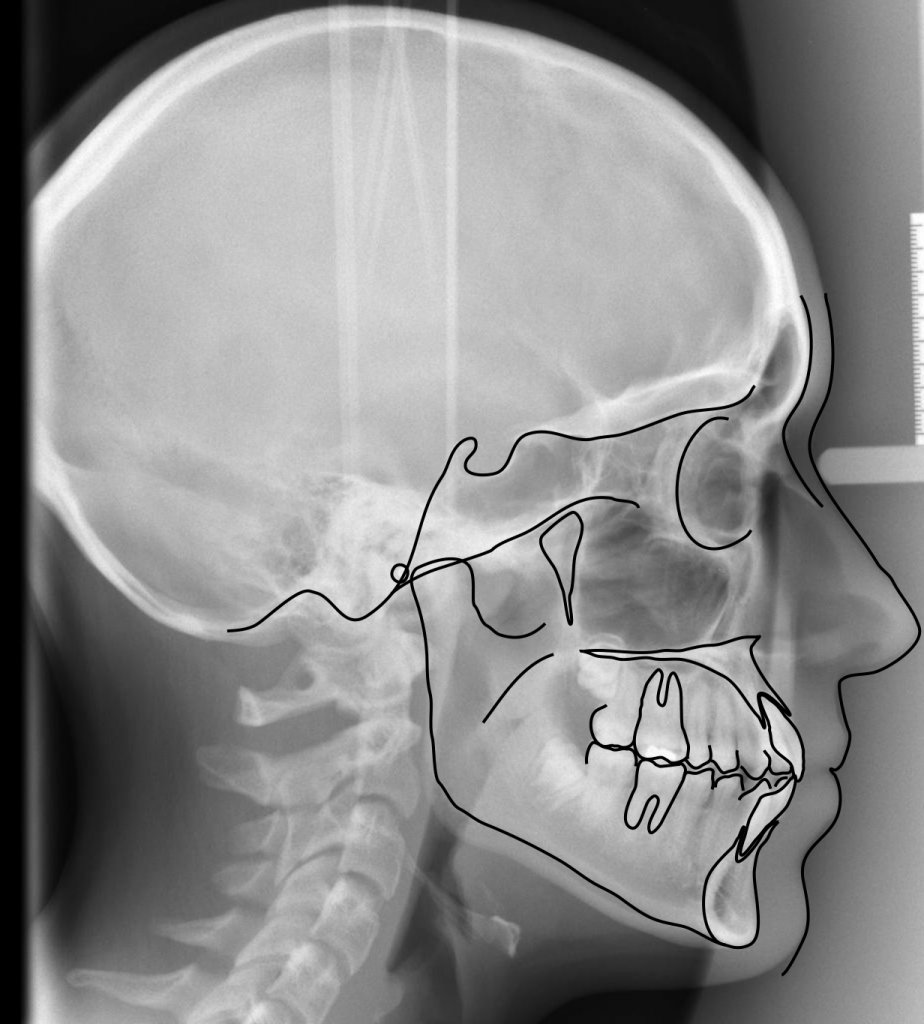

CEPHALOMETRIC ANALYSIS

Cephalometry is a method of making measurements from radiographs. The linear and angular measurements are made and compared to “normal limits” for proper diagnosis and treatment planning. They describe the relationships of tooth to tooth, tooth to bone, and bone to bone. You will need to be able to identify some of the anatomical landmarks and angle measurements, and be able to compare them with established normal limits, to make a determination about the diagnosis and treatment. A series of films can show growth and development. Soft tissue points can be used as well (nose, lips, chin).